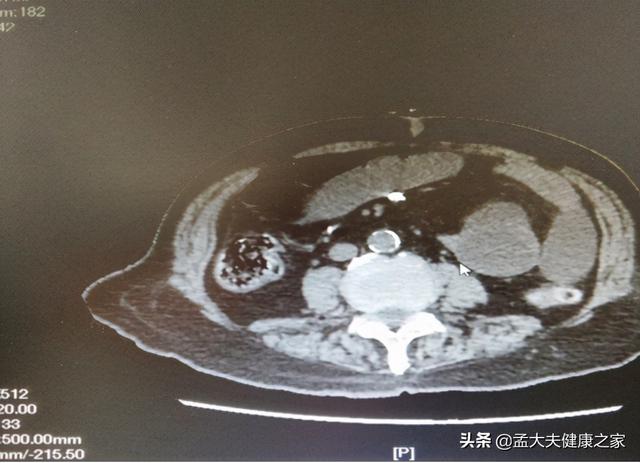

手术治疗.十二胃溃疡未及时治疗,等待病情发展到最后阶段,极有可能会造成癌变,引发胃癌.因此,在确诊之前,有必要去专科医院进行详细的胃镜检查。胃镜检查是目前检查胃健康最有效的手段,可以直接反映胃的最真实情况,为以后的治疗提供有利条件。

早期的胃癌患者可以在胃镜下进行病灶切除手术,从而保证了部分完整的胃部结构和胃功能。同时,胃部病灶切除术需要有一定的技术含量,建议患者去到大医院接受正规手术治疗,千万不要去资质差的医院诊治,以免造成不良后果。

除了胃镜手术外,常见的应是开腹手术。开腹手术包括了胃的切除,淋巴结清除和消化道重建几个环节。医生根据患者的肿瘤位置以及大小,有针对性的手术切除;另外,完成手术后患者是能够正常饮食的,不受手术影响。